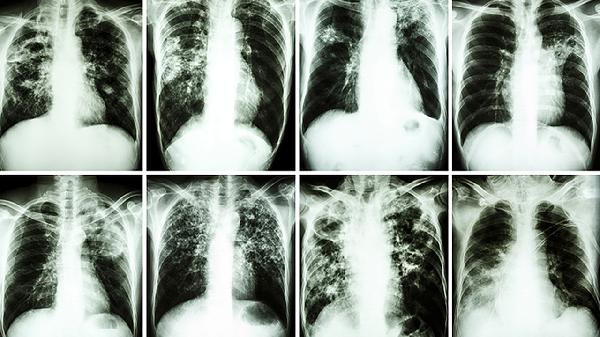

X线检查主要为早期食道肿瘤的病变。舌质淡黯,舌苔薄白,脉弦细。

主证:症状单纯,轻度梗噎或吞咽不利。X线检查多属早、中期髓质型、蕈伞型食管癌。舌质黯青,苔黄白,脉弦细。

主证:症状除吞咽不利外,以胸痛为主,且痛有定外,或伴口臭等。X线检查多为中、晚期髓质型、溃疡型食管癌。舌质紫黯,舌面有瘀点或瘀斑,舌下静脉怒张,舌苔黄腻,脉沉涩而紧。

主证:吞咽困难,痰涎壅盛,胸咽噎塞,膈肋胀满,浊气上逆,舌质黯青,舌体肥大,周有齿印,苔白厚腻多津,脉象滑细。X线检查多为晚期髓质型、缩窄型食管癌。